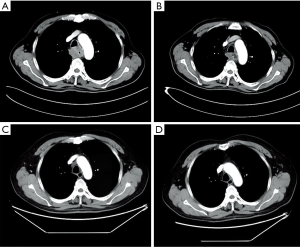

Considering the high risk of surgery, the patient received nasogastric tube placement and chemotherapy involving the administration of docetaxel (120 mg, day 1), nedaplatin (60 mg, days 2–3). After 3 cycles of chemotherapy, the lesion did not shrink obviously on chest enhanced CT (Figure 2A). In view of the good objective response rate (ORR) of camrelizumab in the phase 1 trial, the patient agreed to receive immunotherapy with camrelizumab. After 1 cycle of monotherapy with camrelizumab, the lesion shrank slightly based on chest CT (Figure 2B). Therefore, another 2 cycles of monotherapy with camrelizumab were administrated. To further improve the efficacy, the patient received 8 cycles of combination therapy with camrelizumab (200 mg day 1) and docetaxel (120 mg day 2) from November 2017. In January 2018, the nasogastric tube was removed. The patient can take some semi-liquid food. Then, 6 cycles of monotherapy with docetaxel as maintenance therapy were administrated. On August 17, 2018, there was no abnormal lesion found in the esophagus according to chest CT (Figure 2C). Dysphagia score improved to 1 score. On April 22, 2019, complete response was still observed on chest CT (Figure 2D). On November 14, 2019, the gastroscope examination indicated smooth mucosa of the esophagus (Figure 1B). Temporary grade II adverse event of reactive capillary hemangioma was observed during the treatment. By November 14, 2019, the PFS exceeded 28 months, and the patient is still being followed up. The treatment processes of the patient were shown in Figure 3.